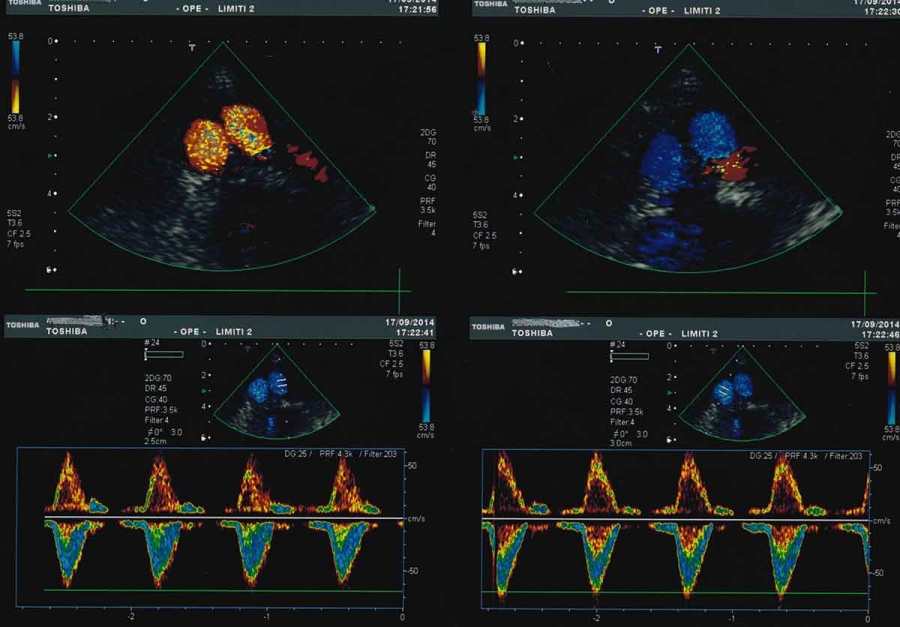

Ecocolordoppler dell’aorta addominale

L’esame ecografico dell’aorta addominale ha principalmente lo scopo di identificare per tempo la dilatazione ( aneurisma ) di questa grossa arteria. L’esame consiste nell’appoggiare una sonda ecografica sull’addome, da sotto lo sterno fino all’ombelico, e nella registrazione delle immagini e dei grafici doppler.

L’esame semplice e privo di radiazioni serve pertanto ad individuare tale patologia, seguirla nel tempo e, quando necessario, porre l’indicazione ad un intervento chirurgico ( aneurismectomia ). Con la metodica in oggetto, in casi selezionati, si può anche verificare la possibilità di un’intervento mediante applicazione di endoprotesi.